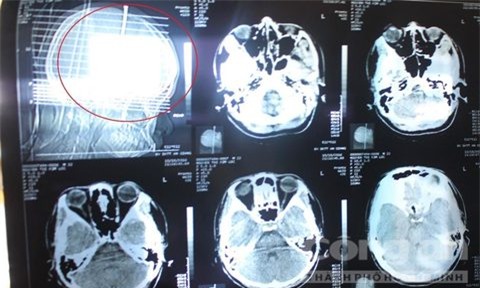

Do giận cha không cho xem TV, Lộc đã tự ý lấy cây đinh dài khoảng 7cm đóng vào đầu cách nay 3 ngày.

Sau khi đưa vào bệnh viện, bệnh nhân được bác sĩ lấy cây đinh ra khỏi đầu và giữ lại để tiếp tục theo dõi. Hiện Lộc đã qua cơn nguy kịch và có thể nói chuyện với người nhà.